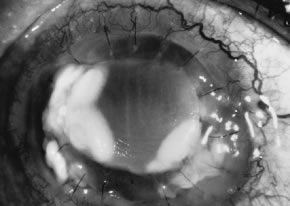

Candida infection typically produces epithelial ulceration, focal necrotizing stromal inflammation, moderate cellular infiltrate and edema in the adjacent stroma, and mild or moderate iritis in the early stages, indistinguishable from bacterial keratitis (Figs. 15, 16, and 17). Fungal elements cannot be detected by biomicroscopy. If untreated, the keratitis evolves to produce dense suppuration and necrosis of the deep stroma. Although multifocal suppuration may develop in polymicrobial keratitis, there is no distinctive sign of mixed Candida and bacterial infection (Fig. 18).

Fig. 15. C. albicans keratitis in an eye following chronic use of corticosteroid drops for herpes simplex keratitis. Note the central suppuration and perforation, endothelial plaques, and hypopyon.

Fig. 16. C. albicans following penetrating keratoplasty in a woman with severe rheumatoid arthritis. Chronic application of corticosteroid eye drop. Note the area of dense, opaque white suppuration that straddles the graft-host junction.

Fig. 17. C. albicans in a 21-year-old woman. Topical proparacaine hydrochloride abuse. Epithelial and stromal ulceration. Note the dense, white area of necrotizing stromal keratitis.

Fig. 18. C. albicans and Streptococcus keratitis in a woman following chronic application of corticosteroid eye drops. Note the separate area of suppurative keratitis. Both organisms were isolated from the separate foci.